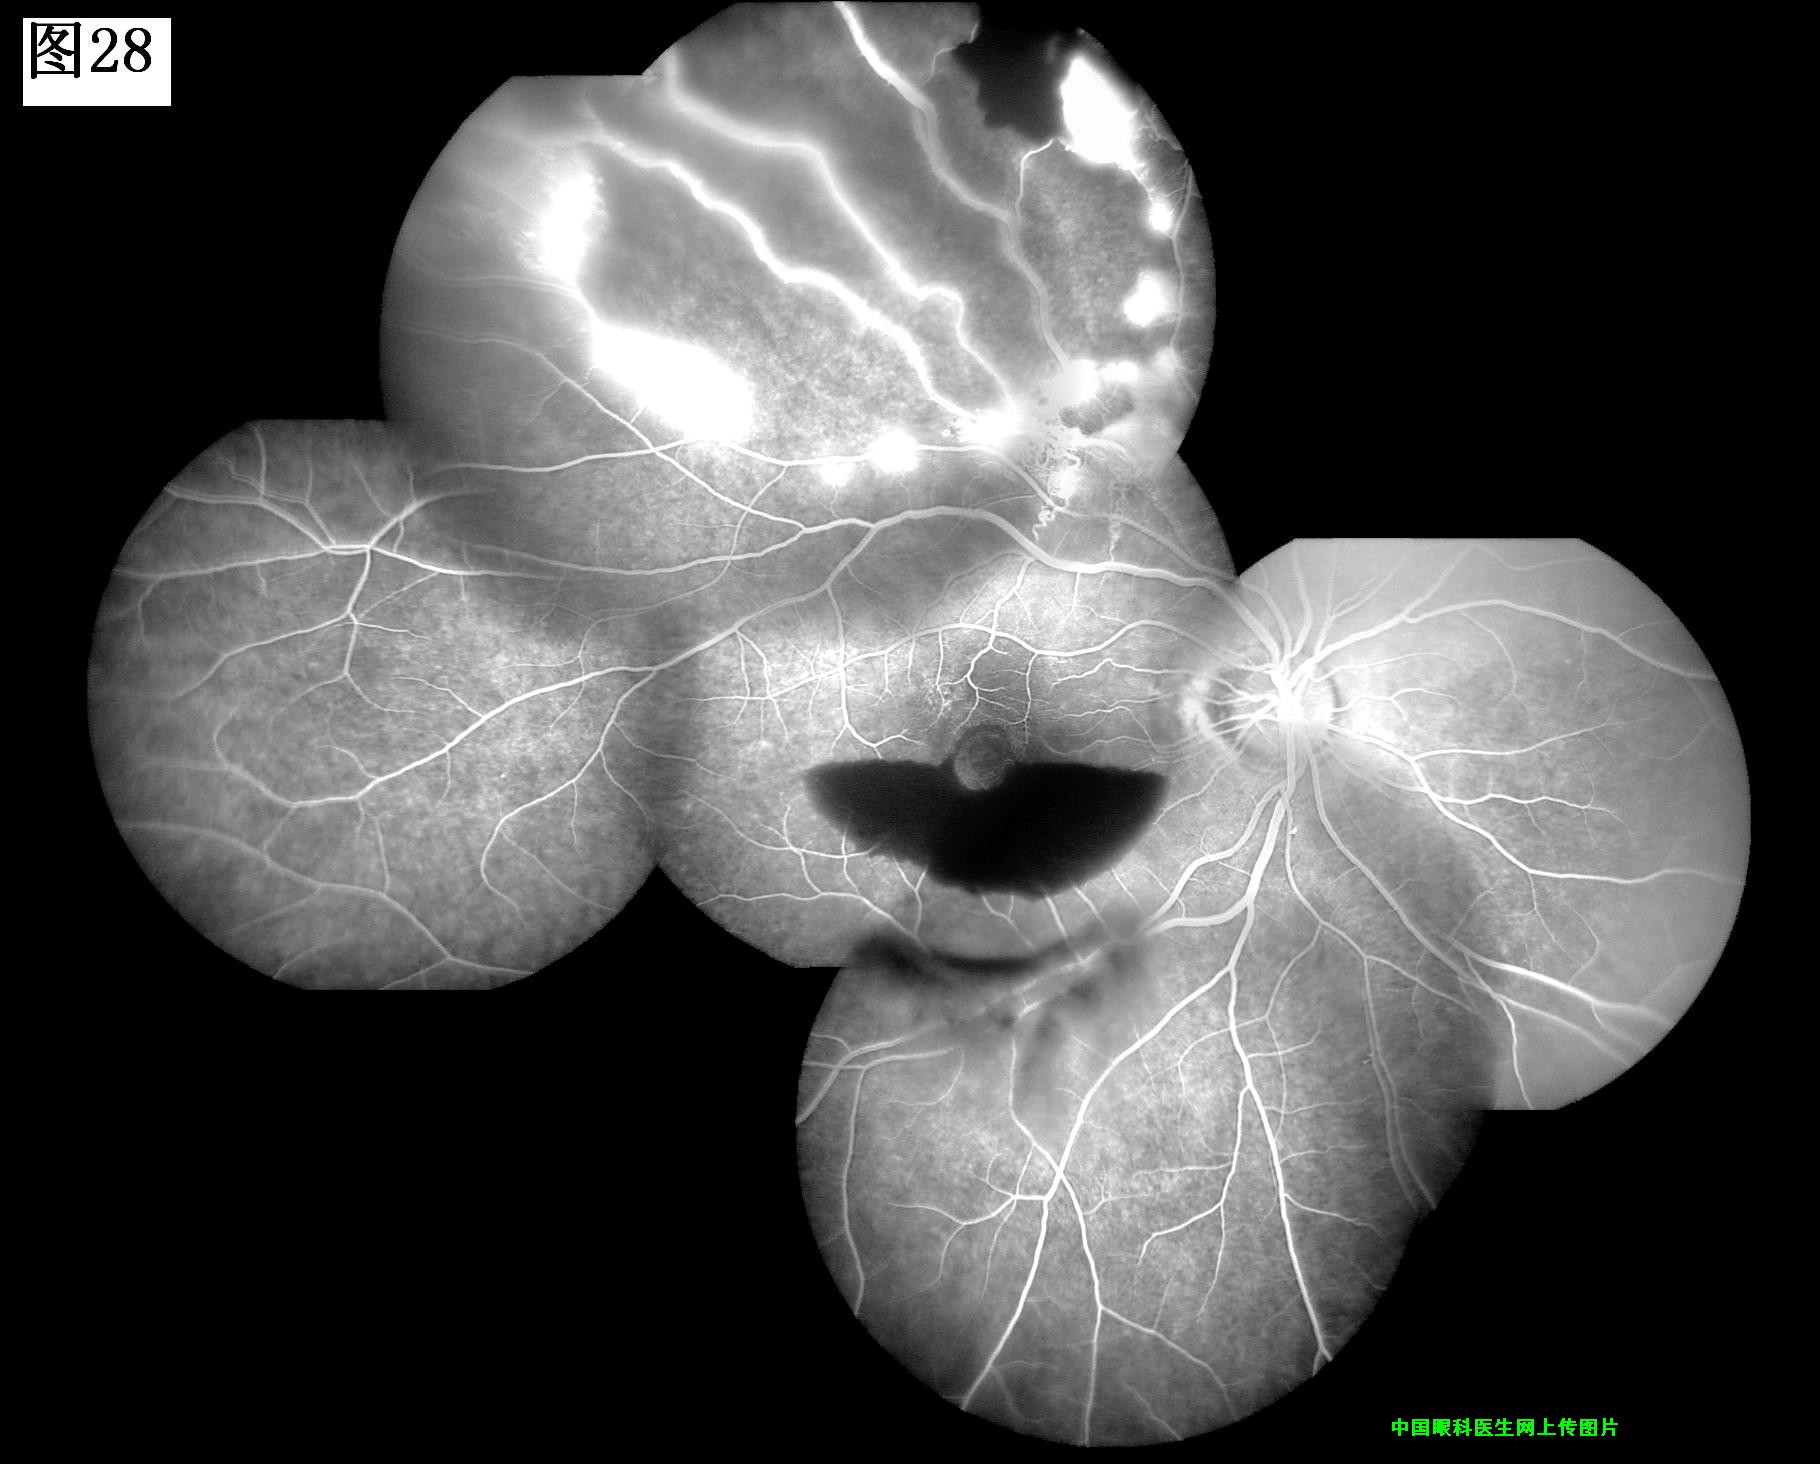

25 26 27 28